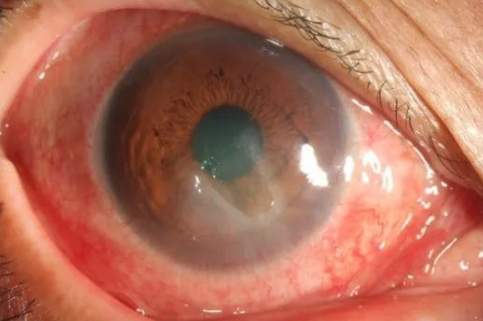

5. Neurogenic corneal epithelial lesions are often caused by the damage of the trigeminal nerve, such as surgery, trauma, tumor, etc. because the sensitivity of the cornea that loses trigeminal innervation decreases, and the protective mechanism of the cornea weakens, it is easy to be damaged. At the same time, the loss of innervation leads to corneal epithelial dystrophy, and the repair mechanism is weakened. The typical clinical feature is that the signs are heavier than the symptoms, and most patients have no serious eye pain, tears and other irritating symptoms, which is related to the decline of corneal perception after trigeminal nerve injury.

Figure 6. A 56 year old female patient complained of right eye redness, but no eye pain and tears. She had a history of trigeminal neuralgia surgery 3 years ago and was diagnosed as neurotrophic keratitis